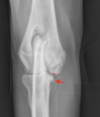

16

What is shown in this radiograph at the arrows?

A

Codman’s triangle

What is Codman’s triangle?

-solid periosteal reaction seen at the edge of an aggressive reaction

-not pathognomonic for tumors